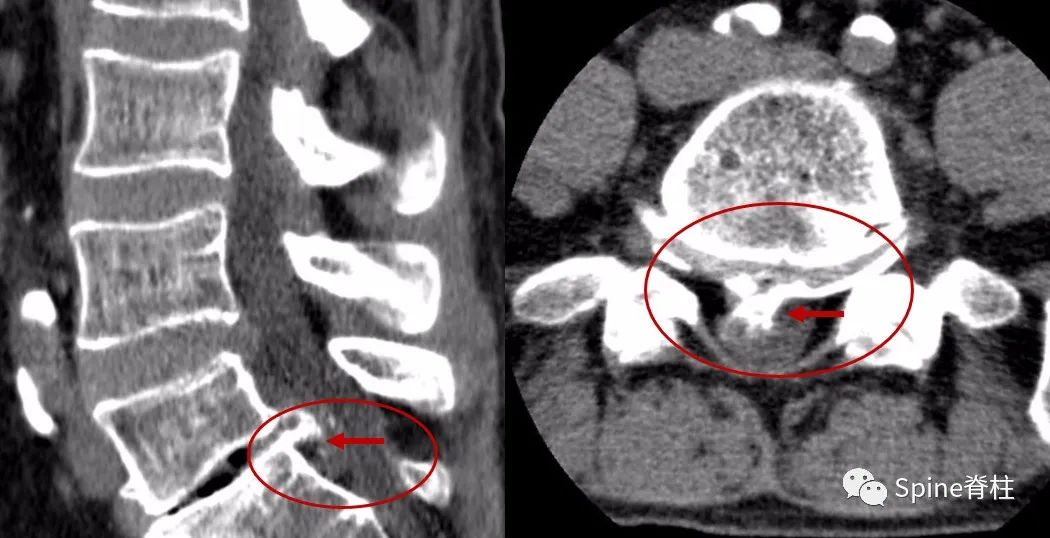

另外,需要明确的是,CT和MRI都是躺着拍的,而X线是站者拍的。对于需手术的腰突症患者,拍X线片可从整体评估腰椎结构、序列,尤其对腰椎滑脱的诊断意义更大,因为平躺后滑脱可能会自行复位,此时拍CT和MRI会导致漏诊。另外,MRI对骨质的分辨要差于CT,对于伴有骨化的椎间盘突出,手术难度要明显大于单纯的软性髓核突出。术前CT可甄别骨化的椎间盘,有助于评估手术难度(图10)。

图10:腰椎CT示L5-S1椎间盘突出伴骨化

因此,建议需手术治疗的腰椎间盘突出症患者,完善腰椎X线、CT和MRI平扫,可全面评估腰突情况,为顺利手术保驾护航。